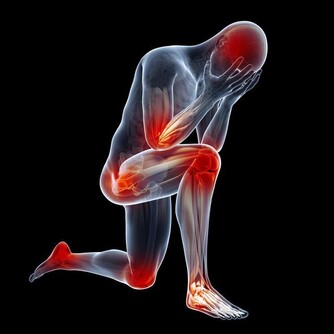

胸口疼,很多人都經歷過,而且隨著現在的生活工作壓力越來越大,

這種疾病發病率也越來越高,

由於很多時候心口疼很快會好轉,以至於很多人都沒有放在心上。但是,導致胸痛的原因多種多樣,疼起來的劇烈程度也不一樣,

有的可能並不緊急,過一段時間就能自愈,而有的可能會危及性命。

所以在胸口疼時,能夠及時判斷原因,採取有效的措施,進行及時的治療,才能避免出現嚴重的後果。